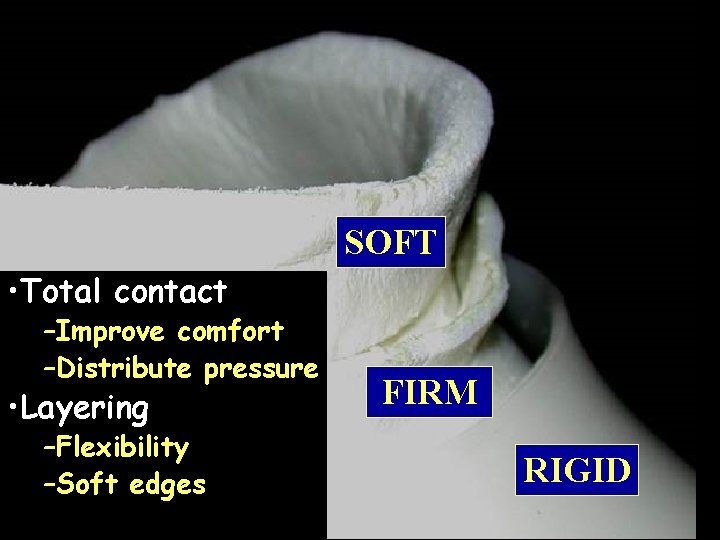

SOFT • Total contact –Improve comfort –Distribute pressure • Layering –Flexibility –Soft edges FIRM RIGID